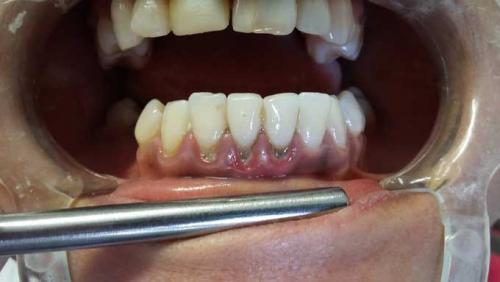

Черные точки на небе. Почему темнеют десны

Темные пятна могут появляться на любом участке десны. Они бывают большие и маленькие, точечные и протяженные.

Причины появления черных пятен на деснах:

- Курение (самая распространенная причина).

- Кариозное поражение зуба.

- Зубной камень.

- Гингивит, пародонтит с кровоточивостью.

- Воспаление слизистой оболочки рта (стоматит).

- Физическая травма челюсти, десны.

- Пломбировка зуба амальгамой.

- Синдром Пейтца-Егерса.

- Болезнь Аддисона.

Синдром Пейтца-Егерса и болезнь Аддисона — заболевания очень редкие. Об их наличии у человека известно с раннего детства. Одним из симптомов патологий является появление черных точек или пятнышек на небе, деснах, языке, губах.

Курение и темные десны

Постоянное действие никотина и смол оказывает пагубное влияние на весь организм, а на ротовую полость особенно. Почти все курильщики имеют следующие симптомы:

- черные пятна на деснах;

- изменение оттенка зубной эмали (смена на желтый или серый цвет);

- неприятный запах из ротовой полости ;

- привкус горечи во рту.

Десна курильщика всегда темные и с различными заболеваниями